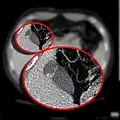

CT scan showing a phrygian cap

The Phrygian cap results from folding of the gallbladder fundus.